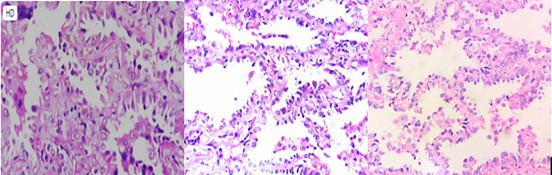

* Kết quả GPB các bệnh phẩm sau mổ: Chi tiết hình ảnh HE bệnh phẩm sau phẫu thuật đuợc thể hiện trong hình 4.

Mảnh sinh thiết vào vùng mô u chỉ có phần nhỏ phổi lành tính. Vùng nhu mô cho thấy phần nhiều có cấu trúc Lepidic với các tế bào u lót phế nang, thay thế các phế bào. Một số vùng khác có cấu trúc nhú và hoặc dạng tuyến. Các tế bào u loại trụ hay hình khối có nhân tăng sắc, ưa kiềm mạnh, tỷ lệ nhân/bào tương tăng cao. Mô đệm có vùng xơ hoá. Kết luận: UTBMT nổi trội thành phần Lepidic.

Hình 4. Tiêu bản HE bệnh phẩm sau phẫu thuật (số hiệu TB: 4852.B21)